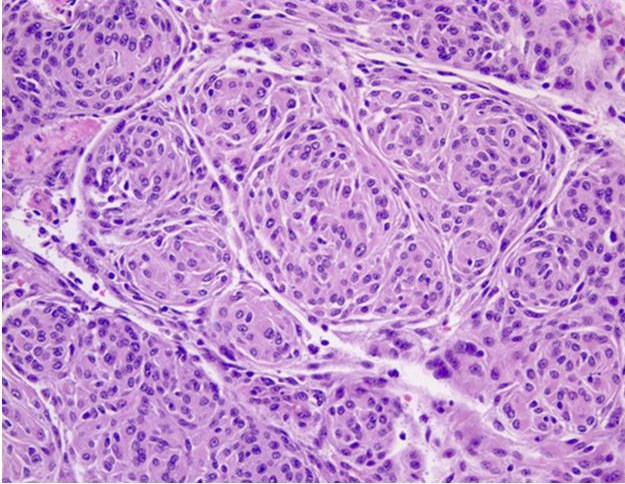

FIGURE 1: Sphenoid wing meningioma (H&E, 20x). Image depicts whorls of meningothelial cells composed of bland epithelioid type cells with eosinophilic cytoplasm arranged in a syncitium. The nuclei are ovoid with vacuoles and pseudo-inclusions.